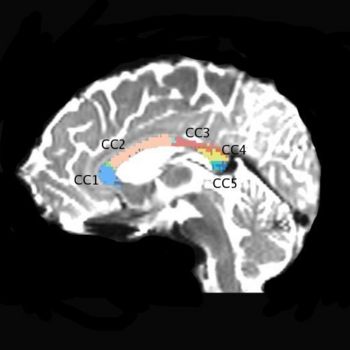

We are using a high resolution 3 Tesla scans, 1.7x1.7x1.7 mm, 51 diffusion directions, 8 baselines (data available to NAMIC investigators). So far we scanned 24 subjects, 12 chronic schizophrenics and 12 matched control subjects. Fiber tractography is performed on the whole brain, and then an automatic clustering method (O’Donnell et al., 2006), is applied. Midsagittal slice is then painted according to anatomical clusters, which results in 5, reliable clusters. Mean FA, mode, trace as well as volume of each clusters are obtained for each subject, and compared between groups.

Preliminary results show a reduced FA in the second cluster (CC2) of the corpus callosum in schizophrenics and a reduced volume in the third cluster (CC3) of schizophrenics, when compared with control subjects.